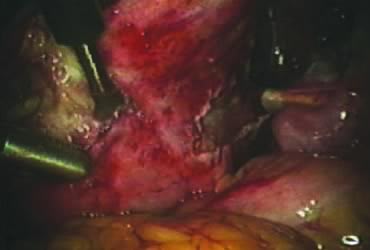

Posterior Dissection

The right ovary is held with the three-prong grasper stretching and exposing the utero-ovarian ligament, which is coagulated and cut in its midportion (Fig. 4). The posterior leaf of the right broad ligament is incised downward to the level of the insertion of the uterosacral ligament in the cervix. The same two steps are repeated on the opposite side and the two sides are connected (Fig. 5).

Fig. 4. Coagulation of the utero-ovarian ligament.

Fig. 5. Incision of the posterior leaf of the broad ligament connecting both sides.